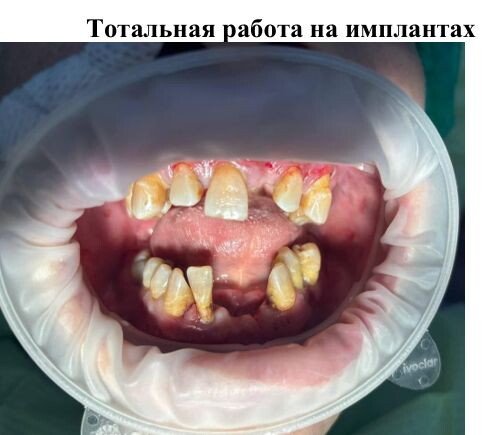

Фотогалерея